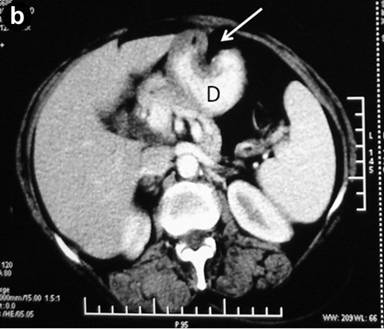

Abdominal ultrasonography showed a distended gallbladder without any calculi, prominent intrahepatic biliary radicals, a (10 mm) common bile duct dilated to the lower end with no calculi, prominent main pancreatic duct and a 2.8x1.9 cm hypoechoic mass near the distal end of the common bile duct. An abdominal computed tomography (CT) scan confirmed the dilatation of the common bile duct and the main pancreatic duct, and revealed an ill-defined hypodense mass 6.5x5.5 cm in size arising from the uncinate process of the pancreas (Figure 1). The mass involved the duodenum with an extension to the duodenojejunal flexure. The proximal duodenum was found to be dilated. The CT scan suggested the diagnosis of a pancreatic mass with duodenal infiltration. Upper gastrointestinal endoscopy was performed showing esophagitis and extraneous compression in the duodenal bulb. A side view endoscopy was performed and showed a long pedicle-like structure extending from the duodenal bulb into the distal duodenum along the medial wall of the second part of the duodenum (Figure 2). The distal end of this structure, the ampulla and the distal duodenal lumen could not be visualized. An attempt was made to pull the distal end of the structure using biopsy forceps but without success. Besides these findings, no ulcers, strictures or growths were found in the duodenum. In view of the endoscopic findings, the CT scan was again reviewed. The mass initially described as originating from the uncinate process was suspected to be intraluminal within the distal duodenum with a smooth outline at the distal end. However, this mass could not be defined as separate from the pancreas. In addition, a characteristic sign of “duodenal wall invagination” was observed in the dilated first part of the duodenum (Figure 3). Barium meal examination of the upper digestive tract showed a well defined smooth lobular filling defect in the dilated first part of the duodenum (Figure 4). Given the above findings, a duodenal polypoid mass of unknown nature was suspected. A side view endoscopy was repeated and endoscopic ultrasonography (EUS) was also performed. During this examination, a large polypoid mass with normal overlying mucosa was seen in the proximal duodenum (Figure 5a). The ampulla was seen as separate from the polyp and was found to be normal as was the visualized distal duodenum (Figure 5b). Endoscopic ultrasonography revealed a homogenous echogenic mass occupying the submucosa in the duodenal bulb with a normal pancreas which was not involved by the mass (Figure 5c). A biopsy taken from the polyp showed non-specific changes in the mucosa.

Figure 3. CT scan showing the dilated first part of the duodenum (D) along with the thickening and characteristic invagination of the anterior duodenal wall (arrows: invagination sign). |

They are usually asymptomatic and are discovered incidentally during endoscopy. Symptomatic cases most commonly present with gastrointestinal bleeding and obstruction [3]. Bleeding is often chronic and may be manifested as chronic anemia. Obstructive symptoms usually occur when they are larger than 2 cm [10]. Brunner’s gland adenoma may present with gastric outlet obstruction [11], duodenal obstruction, as in our case, or occasionally with the intussusception of the duodenal wall [12, 13, 14, 15]. The present case had chronic intermittent duodenal obstruction at the duodenojejunal flexure due to the intermittent prolapse of the polyp. This was evidenced by the presence of a dilated duodenum and the symptoms of gastroesophageal reflux. This obstruction was related to the large size of the polyp and, probably, also to duodenal intussusception. Our patient was having recurrent episodes of duodenal intussusception which were present at the time of the initial endoscopy as well as during the CT scan, as evidenced by the invagination of the duodenal wall (Figure 3). However, it was in the early stage and had already been reduced at the time of surgery.